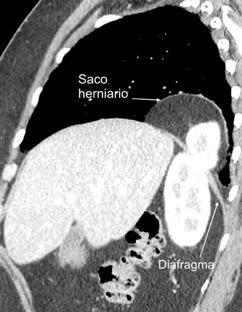

54. QUISTE HIDATÍDICO DIAFRAGMÁTICO

56. ROTURA DIAFRAGMÁTICA. TRAUMA